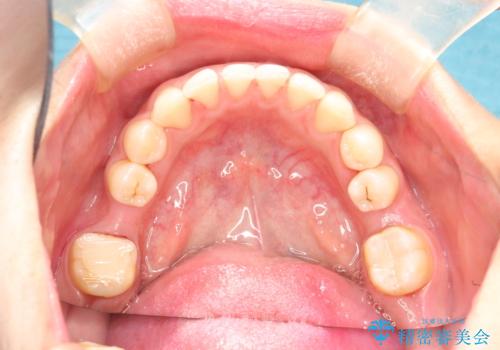

終了時

かなり久しぶりの歯科医院との事で、全体的に古くからの歯垢・歯石が多く付着していたため、自費クリーニング(PMTC)60分コース・歯周ポケット検査(保険適応)を行いました。

磨き残しが放置されると、そこで病原菌が繁殖し始めます。よって歯肉に炎症が生じ、歯周病の原因になることがあります。

定期的に、歯周病検査や専門的なクリーニングをすることで、早期発見につながります。